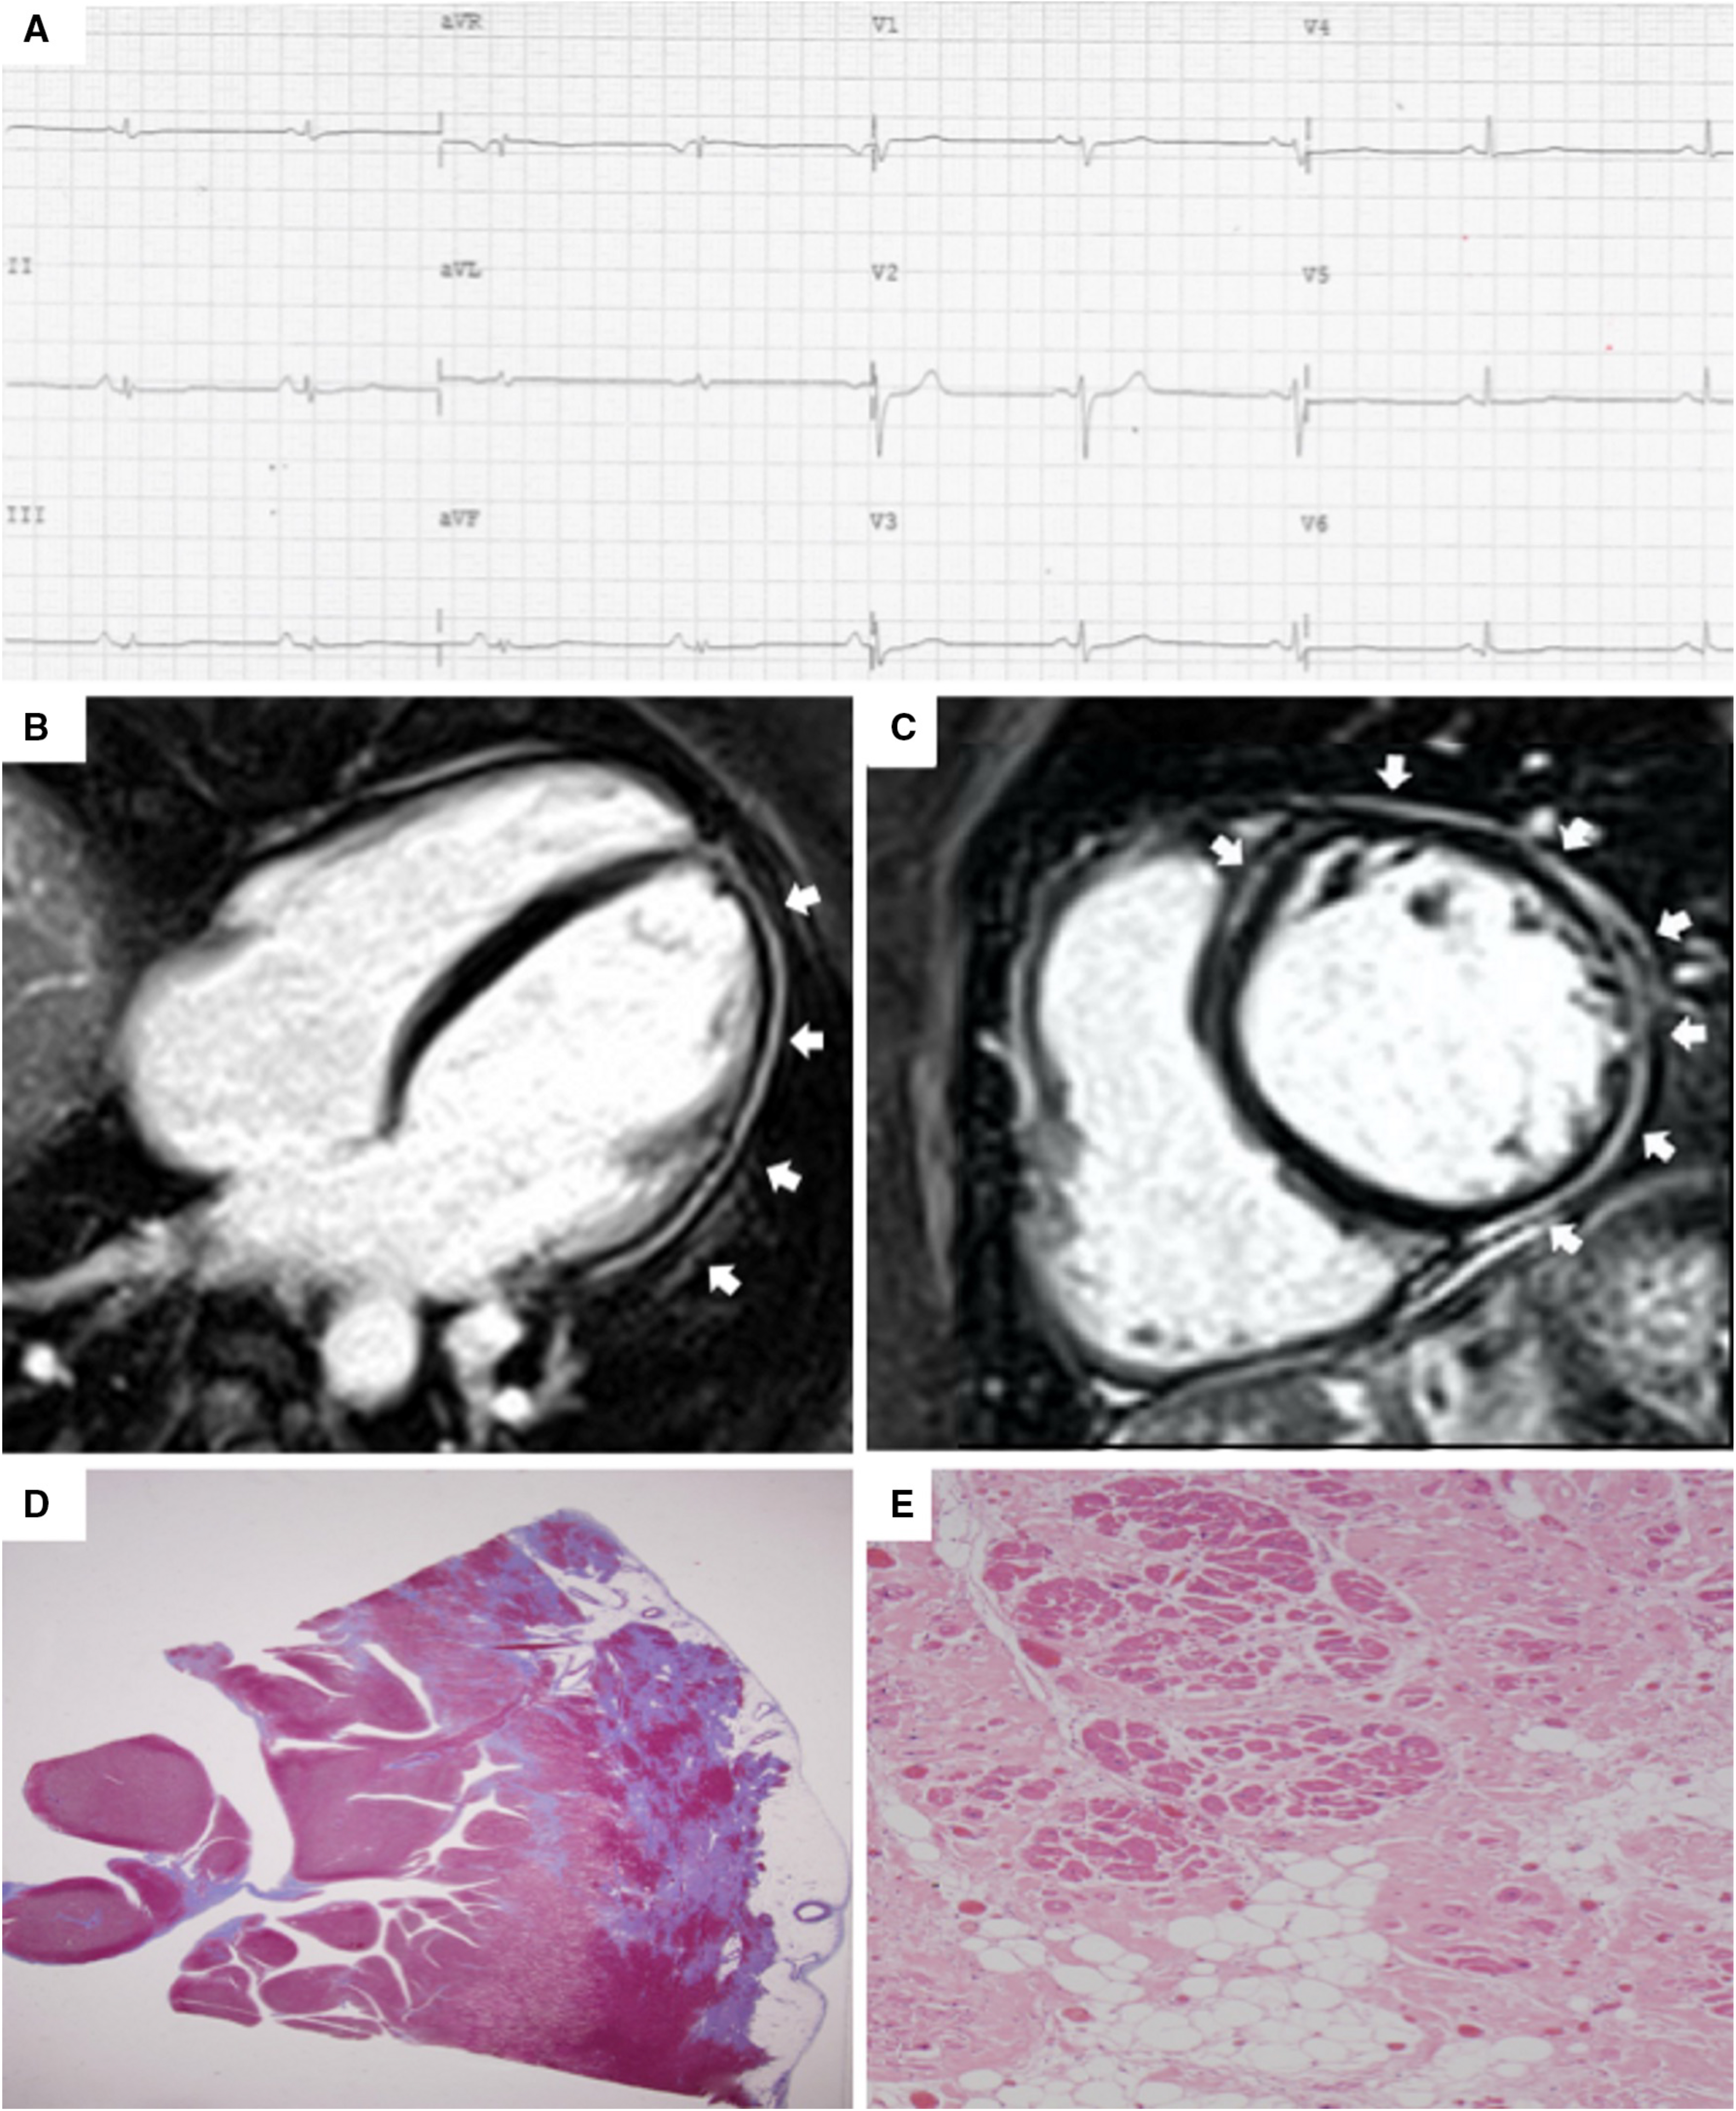

The introduction of non-invasive tissue characterization with CMR is one of the most important innovations of the 2020 criteria. The major CMR criterion is the presence of transmural LGE in at least 1 RV segment, confirmed in 2 orthogonal views. Currently, the diagnostic specificity of RV LGE is considered high, instead the sensitivity is low. This is due to the CMR technology characterized by a poor spectral resolution and suboptimal contrast/noise ratio in quantifying the thin RV wall [17, 28, 29, 30]. The highest specificity is reached when wall motion abnormalities and pre/post contrast signal alterations are considered together [29] (Fig. 3, Ref. [31]).

Fig. 3.Clinical features of ARVC. Basal ECG, exercise testing ECG and CMR findings in a 38-year-old woman hospitalized for sustained VT. Basal ECG showed TWI in V1–V5 and flattened T wave in inferior leads (A). Exercise testing revealed frequent PVBs and a non-sustained VT with LBBB/superior axis morphology, originating from RV free wall (B). CMR revealed mild RV dilatation, moderate RV systolic disfunction, a wide peritricuspid aneurysm, with an extreme thinning of the wall (four-chamber cine view in diastolic phase, C, and systolic phase, D). The PD-TSE sequences revealed fatty infiltration of the RV wall, especially in the subtricuspid region (E, and magnified on the top of F). No RV LGE was identified, not even in the same regions of RV fatty infiltration, maybe because an extreme thinning of the RV wall (F on the bottom). The diagnosis was “definite ARVC”. ARVC, arrhythmogenic right ventricular cardiomyopathy; CMR, cardiac magnetic resonance; LBBB, left bundle branch block; LGE, late gadolinium enhancement; PD-TSE, positron density-turbo spin echo; PVBs, premature ventricular beats; RV, right ventricle; TWI, T wave inversion; VT, ventricular tachycardia. Adapted from Graziano et al. [31].